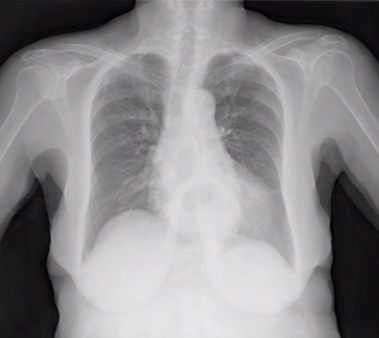

42歳男性。2ヵ月前から左の睾丸が肥大し始めたため泌尿器科外来を受診した。 発熱や寝汗、体重減少、呼吸器症状、尿道分泌物の症状はいずれも認めなかった。 身体所見…